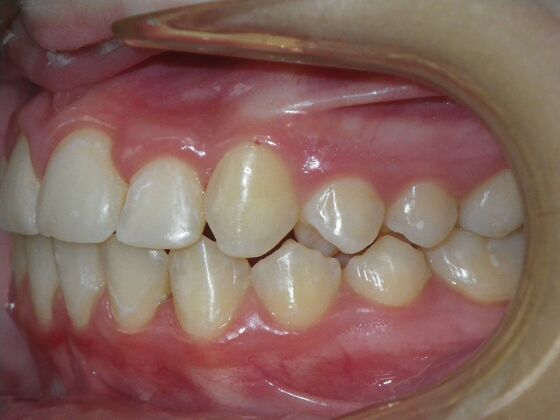

Patient presented with mixed dentition and mild deep overbite, excessive overjet,and rotated lower incisors. She also had a lower bilateral lingual retainer, preventing lower molars from coming forward. She was treated with utility archwires initially, waiting for eruption of cuspids and bicuspids. This was followed by conventional straight wire appliances and upper and lower standard hawley retainers.